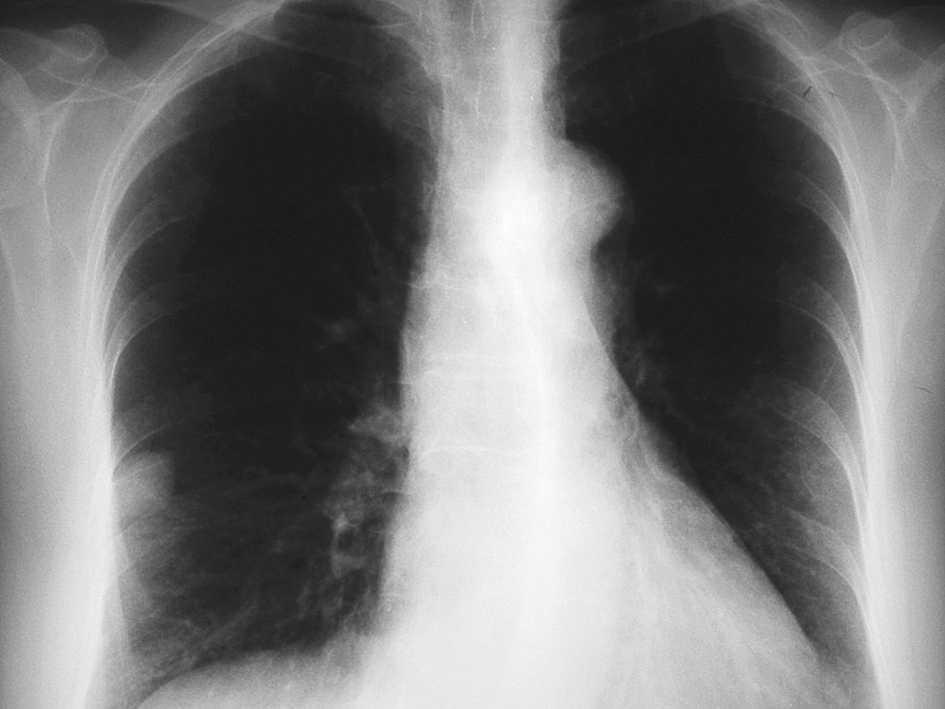

En las pruebas complementarias la analítica (bioquímica, hemograma y coagulación) es normal. Electrocardiograma muestra ritmo sinusal. En la radiografía de tórax (figs. 1 y 2) se aprecia una imagen nodular de 2-2,5 cm localizada en el lóbulo medio derecho (LMD). Con el diagnóstico de bronquitis se cita en la consulta de neumología a la paciente para estudiar la imagen nodular pulmonar de forma preferente, instaurándose un tratamiento broncodilatador y antibiótico.

Figura 1. Radiografía de tórax.